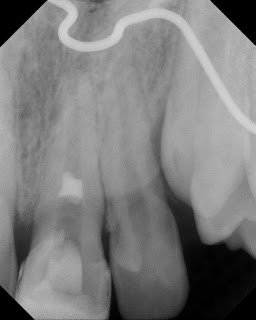

This young patient had a traumatic incident to tooth #9 5 months earlier. At our initial evaluation, the tooth responded normal to thermal testing. We decided to monitor the tooth over time. At a follow up visit, #9 exhibited no response to thermal testing with an open apex.

Pulpal regeneration was started. Complete pulpectomy was performed with minimal instrumentation to the apex, and irrigation with 5.25% NaOCl. A blood clot was initiated into the canal, a collagen plug was placed and an (white) MTA coronal barrier was placed below the level of the CEJ.